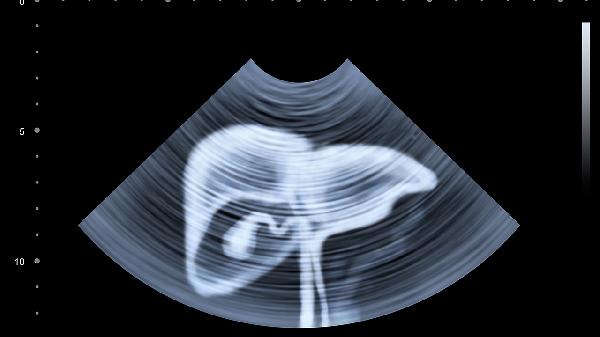

肝脏低密度灶指的是在肝脏影像学检查中发现的密度低于正常肝组织的区域。肝脏低密度灶的严重性因个体差异和具体病因而异。

肝脏低密度灶可能源于良性病变,如肝囊肿或肝血管瘤。这些病变通常生长缓慢,对身体影响较小。例如,肝囊肿是肝脏内的液体积聚,多数无症状且无需特殊治疗,定期复查即可。肝血管瘤则是血管异常增生形成的良性肿瘤,同样在大多数情况下无需干预。

肝脏低密度灶也可能提示更为严重的疾病,如肝癌。肝癌导致的低密度灶通常形态不规则,密度不均匀,且可能伴有肝硬化背景,此时较为严重。这种情况下,进一步的增强扫描、肿瘤标志物检测乃至病理活检都是必不可少的。一旦确诊为肝癌,可能需要手术、化疗等综合治疗。